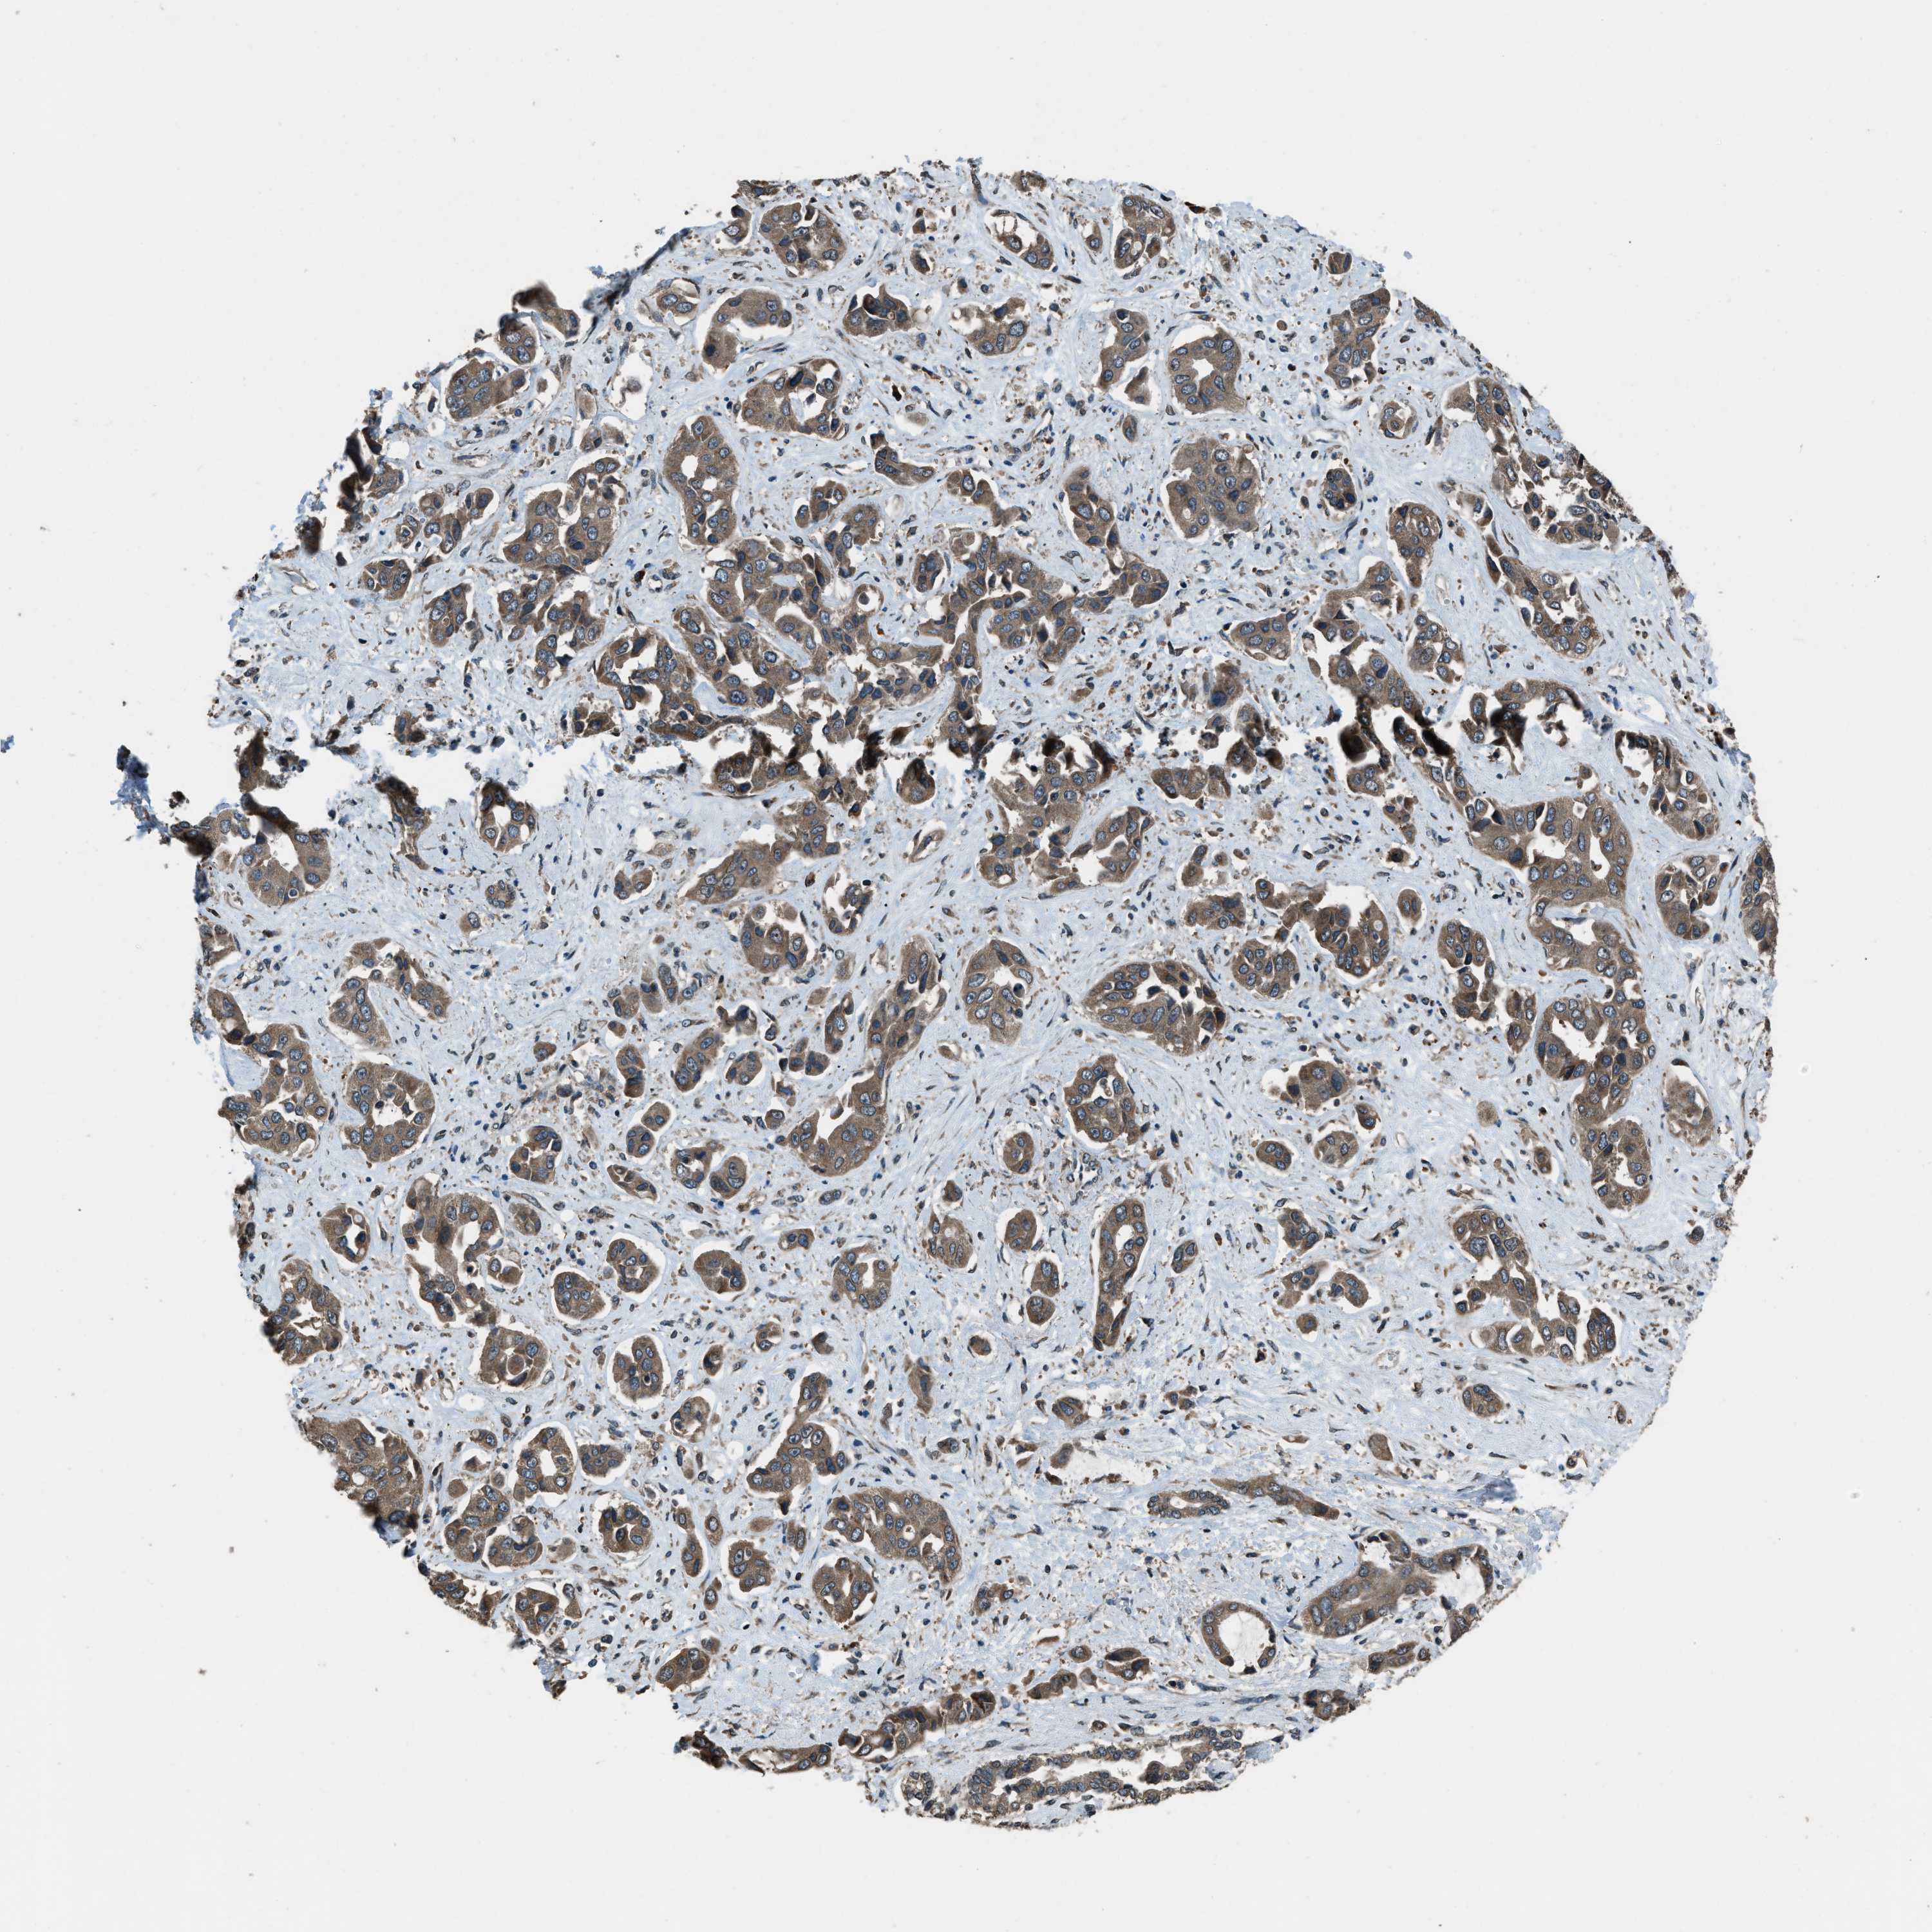

LIVER CANCER - Protein expressioni

A mouse-over function shows sample information and annotation data. Click on an image to view it in a full screen mode. Samples can be filtered based on level of antibody staining by selecting one or several of the following categories: high, medium, low and not detected. The assay and annotation is described here.

Note that samples used for immunohistochemistry by the Human Protein Atlas do not correspond to samples in the TCGA dataset.

Antibody stainingi

Antibody staining in the annotated cell types in the current human tissue is reported as not detected, low, medium, or high, based on conventional immunohistochemistry profiling in selected tissues. This score is based on the combination of the staining intensity and fraction of stained cells.

Each image is clickable and will lead to virtual microscopy that enables deeper exploration of all samples and also displays staining intensity scores, fraction scores and subcellular localization as well as patient and tissue information for each sample.

Antibody HPA019356

Antibody HPA029461

Staining

High

Medium

Low

Not detected

Intensity

Strong

Moderate

Weak

Negative

Quantity

>75%

75%-25%

<25%

None

Location

Nuclear

Cytoplasmic/membranous

Cytoplasmic/membranous,nuclear

Cholangiocarcinoma

Carcinoma, Hepatocellular, NOS